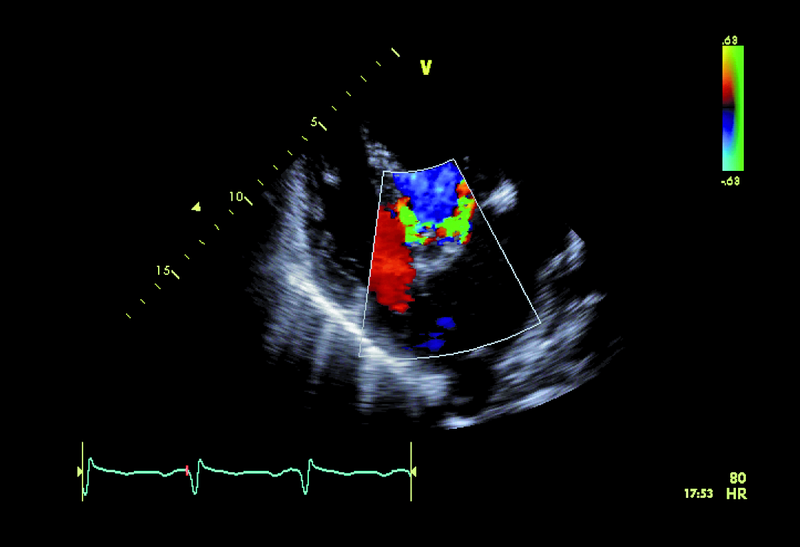

U chłopca, obecnie 16-letniego, wykonano w okresie noworodkowym zabieg operacyjny walwuloplastyki zastawki aortalnej z powodu wrodzonej stenozy. Uzyskano zmniejszenie gradientu maksymalnego z 50 do 16 mm Hg. W ciągu wielu lat obserwacji w ośrodku kardiologii dziecięcej gradienty przepływu przez zastawkę były niskie, a stan kliniczny pacjenta dobry. Sytuacja zmieniła się przed kilkoma miesiącami. Chłopiec został przyjęty do szpitala z powodu męczliwości, szybkiej częstości serca (do 90/min w rytmie zatokowym z pojedynczą ekstrasystolią komorową). Prawdopodobną przyczyną pogorszenia stanu zdrowia była przebyta wcześniej infekcja górnych dróg oddechowych. W badaniu przedmiotowym zwracał uwagę szmer holosystoliczny na koniuszku, promieniujący do pachy. W EKG rejestrowano cechy przerostu i przeciążenia mięśnia lewej komory. Wykonano cewnikowanie serca, stwierdzając nadciśnienie płucne ze średnim ciśnieniem w kapilarach płucnych 29 mm Hg. Pacjent był leczony intensywnie lekami moczopędnymi, beta-adrenolitykami i amiodaronem. Wobec braku poprawy skierowano go na oddział kardiologii dorosłych w celu rozważenia wskazań do leczenia operacyjnego. W badaniu echokardiograficznym zwracały uwagę wąskie strumienie niedomykalności zastawki aortalnej z czasem PHT wynoszącym 206 ms, istotnie powiększona jama lewego przedsionka z powierzchnią około 50 cm2, ciężkie nadciśnienie płucne z ciśnieniem skurczowym w jamie prawej komory 114 mm Hg!, rejestrowanym z małej fali zwrotnej trójdzielnej. Nie stwierdzono wady przeciekowej.

Chłopiec przebył w okresie noworodkowym zabieg walwuloplastyki aortalnej powikłany niedomykalnością zastawki (ryc. 1). Wada miała charakter przewlekły i spowodowała pojawienie się mechanizmów wyrównawczych. Jednym z nich jest zwiększenie objętości lewej komory i przyspieszenie rytmu serca. Frakcja wyrzutowa lewej komory jest zachowana (ryc. 2). Z pewnością infekcja górnych dróg oddechowych była czynnikiem inicjującym niekorzystny dla chorego przebieg zdarzeń. Ocena ciężkości niedomykalności aortalnej na podstawie parametrów ilościowych jest w tym przypadku trudna. Czas połowicznego spadku gradientu ciśnień PHT (aorta – lewa komora) oraz strumień fali zwrotnej w badaniu kolorowego doplera mogłyby wskazywać na umiarkowaną niedomykalność. Nie można jednak zapominać o możliwości zwiększenia ciśnienia rozkurczowego w jamie lewej komory, istotnie zmniejszającego gradient wsteczny i zakres fali zwrotnej. W przypadku dwustrumieniowej fali zwrotnej (jak w tym przypadku) talii cząstkowych niedomykalności nie sumuje się. Podobnie ograniczone zastosowanie w tym wypadku (ekscentryczne fale zwrotne) ma metoda ERO. Najprawdopodobniej wtórną do niedomykalności aortalnej wadą jest niedomykalność mitralna wynikająca z poszerzenia jamy lewej komory i poszerzenia pierścienia zastawki mitralnej. Niedomykalność mitralna także wydaje się co najwyżej umiarkowana (ryc. 3). Należy pamiętać, że i w tym wypadku szerokość strumienia fali zwrotnej zależy od wysokości ciśnienia w jamie przyjmującej, czyli w lewym przedsionku. Na podstawie przedstawionego materiału (ryc. 4-6) można stwierdzić, że nadciśnienie płucne u chłopca (postkapilarne) jest ciężkie, a ciśnienia uległy istotnemu zwiększeniu w porównaniu z wartościami stwierdzanymi wcześniej podczas cewnikowania serca (ciśnienie rozkurczowe płucne 54 mm Hg, średnie 74 mm Hg!). Warto zwrócić uwagę na profil spływu z żył płucnych. Zaznacza się w nim bardzo krótka faza odzwierciedlająca wyłącznie rozkurczowy napływ krwi do lewego przedsionka. Zwiększona objętość jamy przedsionka, wysokie ciśnienie krwi w niej panujące oraz ograniczona podatność ściany sprawiają, że w fazie skurczu komory nie rejestruje się napływu do jamy przedsionka. Podobnie bardzo wysokie ciśnienie w układzie żył płucnych sprawia, że nie obserwuje się przepływu wstecznego w związku z ciągle zachowanym skurczem przedsionka (rytm zatokowy). Chłopca zakwalifikowano do operacji dwuzastawkowej z powodu ciężkiej niedomykalności aortalnej i mitralnej. Zabieg implantacji zastawki biologicznej o średnicy 23 mm w ujście aortalne oraz pierścienia o średnicy 32 mm w ujście mitralne przyniósł dobry efekt.